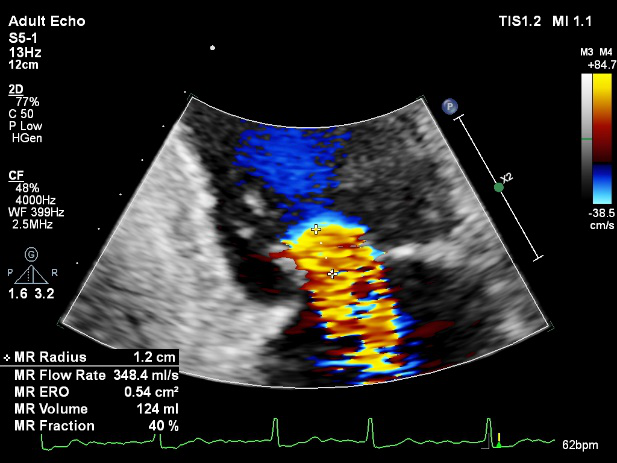

TEE LVOT切面返流量评估

TEE 4-Ch view返流量评估

LVOT-color:MR(重度),返流面积11.3cm2

肺静脉血流频谱呈收缩期反向

3D-color MV view:血流主要来源于2、3区

Qlab软件勾画估测瓣口面积约:6.16cm2